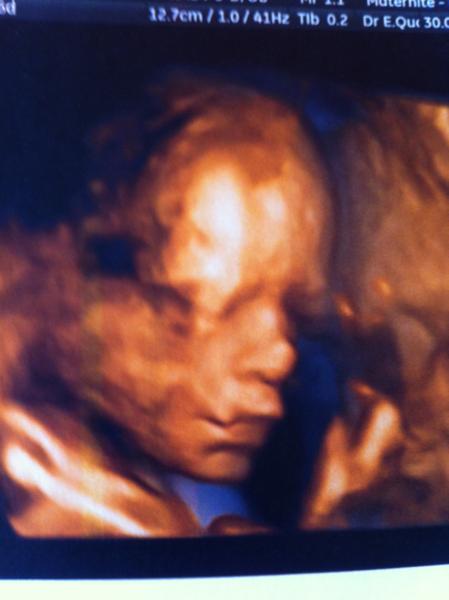

Salut les filles je reviens de mon écho bb va super bien il fait 900 gr voilà une photo

wouaaw trop belle la photo :happy: tu dois etre contente de le voir aussi bien ton ptit mec !!!!

900g a combien de Sa ?

Magnifique ton Bb =)